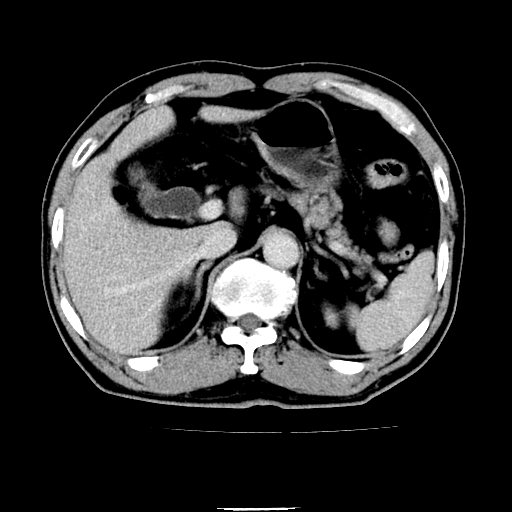

以下是引用chenqiong在2010-3-25 20:56:00的发言:[br]1、胆囊炎,胆囊息肉[br]2、肝内胆管及胆总管扩张,胆总管下端结石[br]3、十二指肠乳头旁憩室

以下是引用zxl51642在2010-3-26 10:47:00的发言:[br]胆囊炎,胆囊息肉,胆总管扩张,但未看到明显肿块,肝内胆管扩张不像恶性,炎性狭窄或阴性结石可能吧,建议mrcp,右肾小囊肿